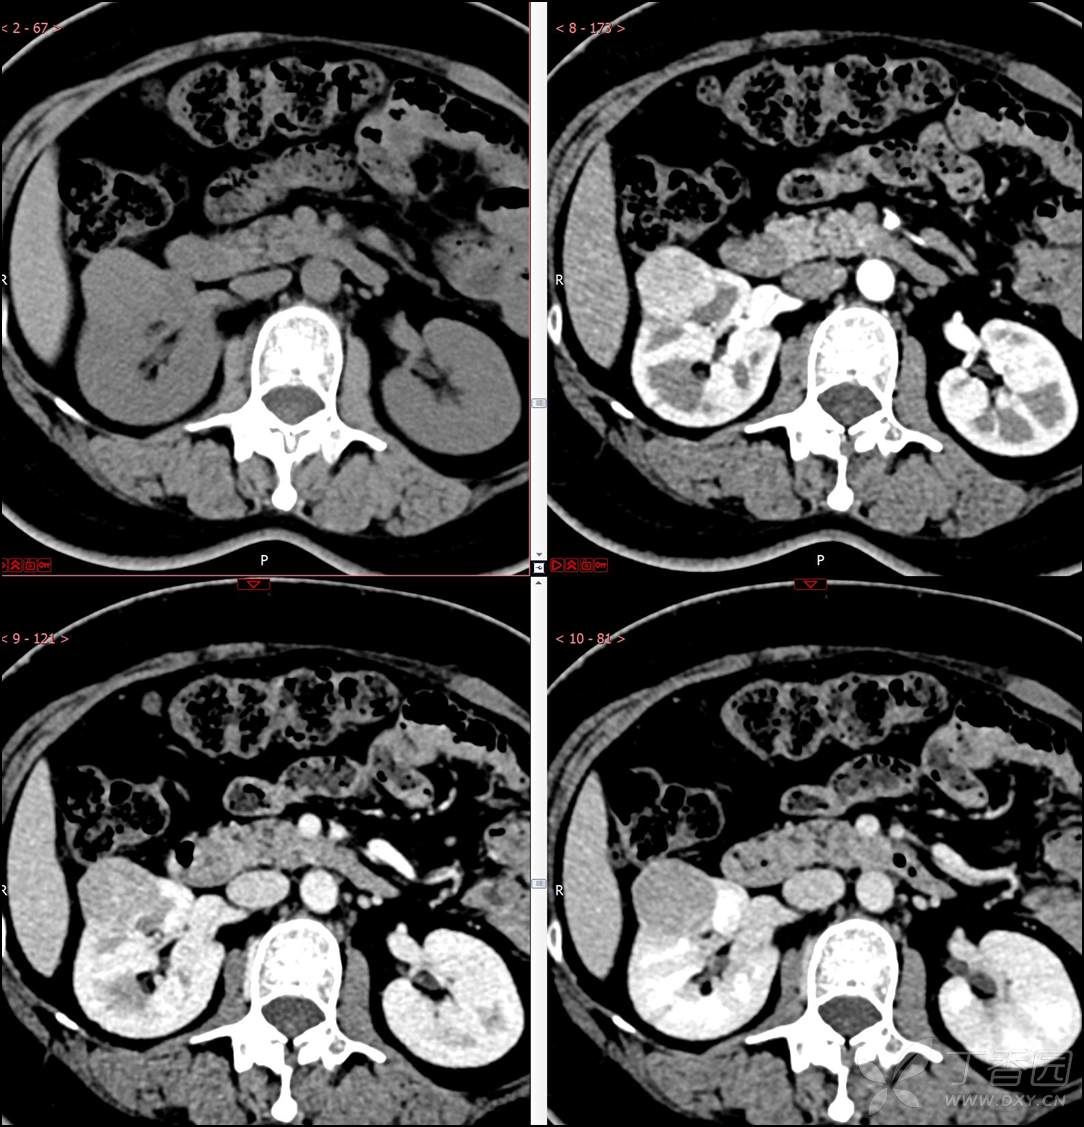

【影诊笔记516】中年女性,检查发现肾占位2周就诊~『嗜酸细胞腺瘤』

主诉:检查发现肾占位2周

简要病史:患者2周前体检发现肾实质性占位,无腰痛,无血尿,无尿频、尿急、尿痛,无发热,在外未行特殊治疗。患者为行进一步治疗就诊于我院,门诊以“肾占位性病变 ”收入我科,患者自发病以来,神志清,精神可,小便如上所述,大便正常,体重无显著变化。